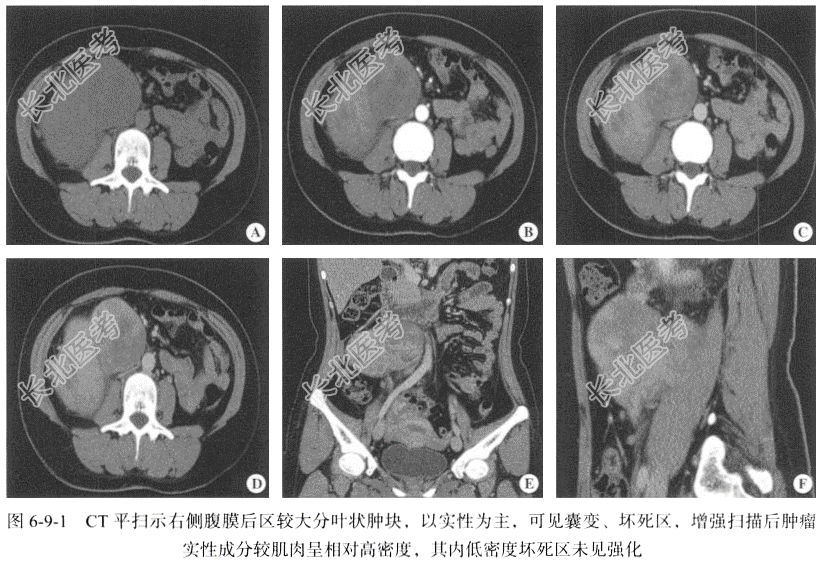

【影像图片】见图6-9-1。

【腹部CT检查】仰卧位,横断位扫描,包括平扫及三期增强扫描及冠状位、矢状位三维重建,扫描范围自膈肌至耻骨联合以下,扫描层厚为5mm,层间隔0.5mm。